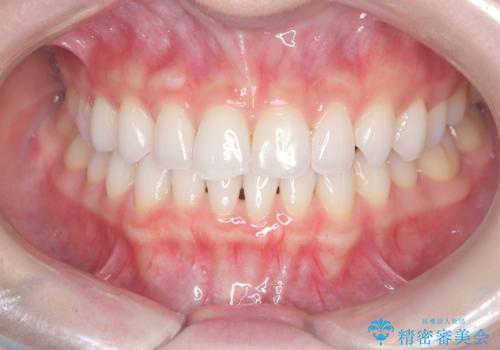

前歯のガタガタを治したい。

- 凸凹を治したいと来院された患者様です。

インビザラインにて、遠心移動を行いながら綺麗に配列することができました。